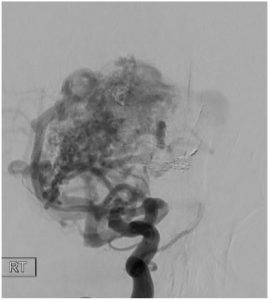

מחלה זו מתאפיינת בחיבור חולני בין עורקים לוורידים מוחיים, מה שגורם להפרעה בתפקוד המוח ועלול לגרום לדימום מוחי, לכאבי ראש, לחסר נוירולוגי מוקדי (כגון חולשת פלג גוף, הפרעה בדיבור וכו') או לפרכוסים אפיליפטיים. צנתור מוח ע"י אמבוליזציה (תיסחוף) מהווה קו הטיפול הראשון המקובל בעולם, וזו השיטה בה משתמש ד"ר רפאלי, באמצעות הזרקת דבק ביולוגי דרך צנתר זעיר, המועלה דרך דיקור עורק ראשי במפשעה עד למוח, למרכז ה – AVM המכונה נידוס, תוך סגירה הדרגתית של העורקים המזינים והוורידים המנקזים את המלפורמציה

האמבוליזציה מתבצעת בצנתור תחת שיקוף רנטגן, במהלכו מועלה צנתר זעיר שקוטרו כ-0.3 מ"מ אל עורקי המוח עד למרכז ה-A.V.M. (הנידוס) . דרכו מוזרק חומר ניגוד המאפשר לזהות ולהבין את תבנית הזרימה בכלי הדם המזינים את הנגע, אופן הניקוז הורידי. כמו כן צריך לזהות גורמי סיכון לדימום כגון מפרצת בעורק המזין או בתוך הנידוס, או הצרות בוריד המנקז. לאחר מכן מוזרק חומר נוזלי אמבולי – למעשה דבק ביולוגי – וכך מתאפשרת סגירת מקלעת כלי הדם והחיבורים החולניים בין עורקים לורידים.